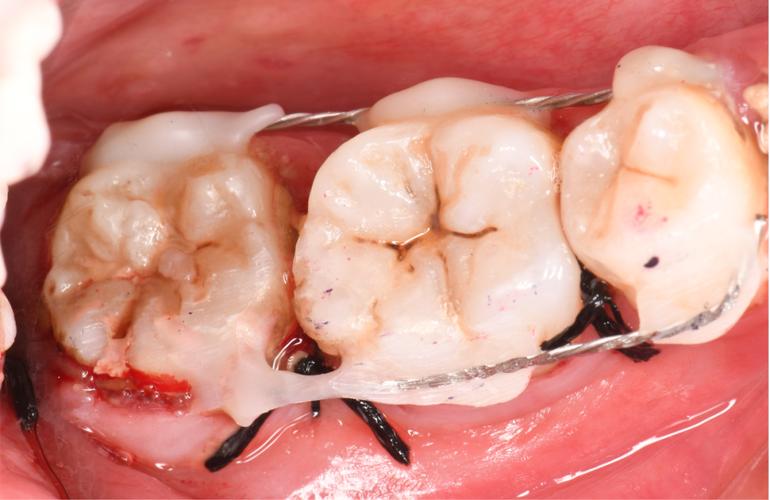

骨移植与种植体植入

获取自体骨后,需将其处理并移植至骨缺损区域,若骨缺损较大,可配合生物膜(如胶原膜、钛膜)覆盖,防止软组织长入,引导骨组织再生,根据骨愈合情况,种植体植入可分为两种方式:

- 同期植入:适用于骨缺损较小、骨质量较好的患者,即在骨移植后立即植入种植体,减少手术次数;

- 延期植入:适用于骨缺损严重、需大量骨移植的患者,待移植骨与宿主骨完全愈合(通常3-6个月)后再植入种植体。